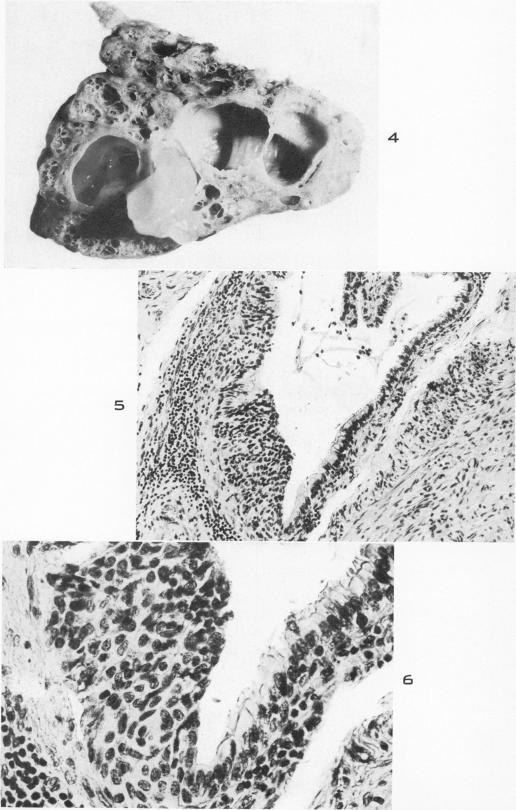

Minute peripheral pulmonary tumors; observations on their histogenesis.

Am J Pathol. 1953 Jul-Aug;29(4):703-19.